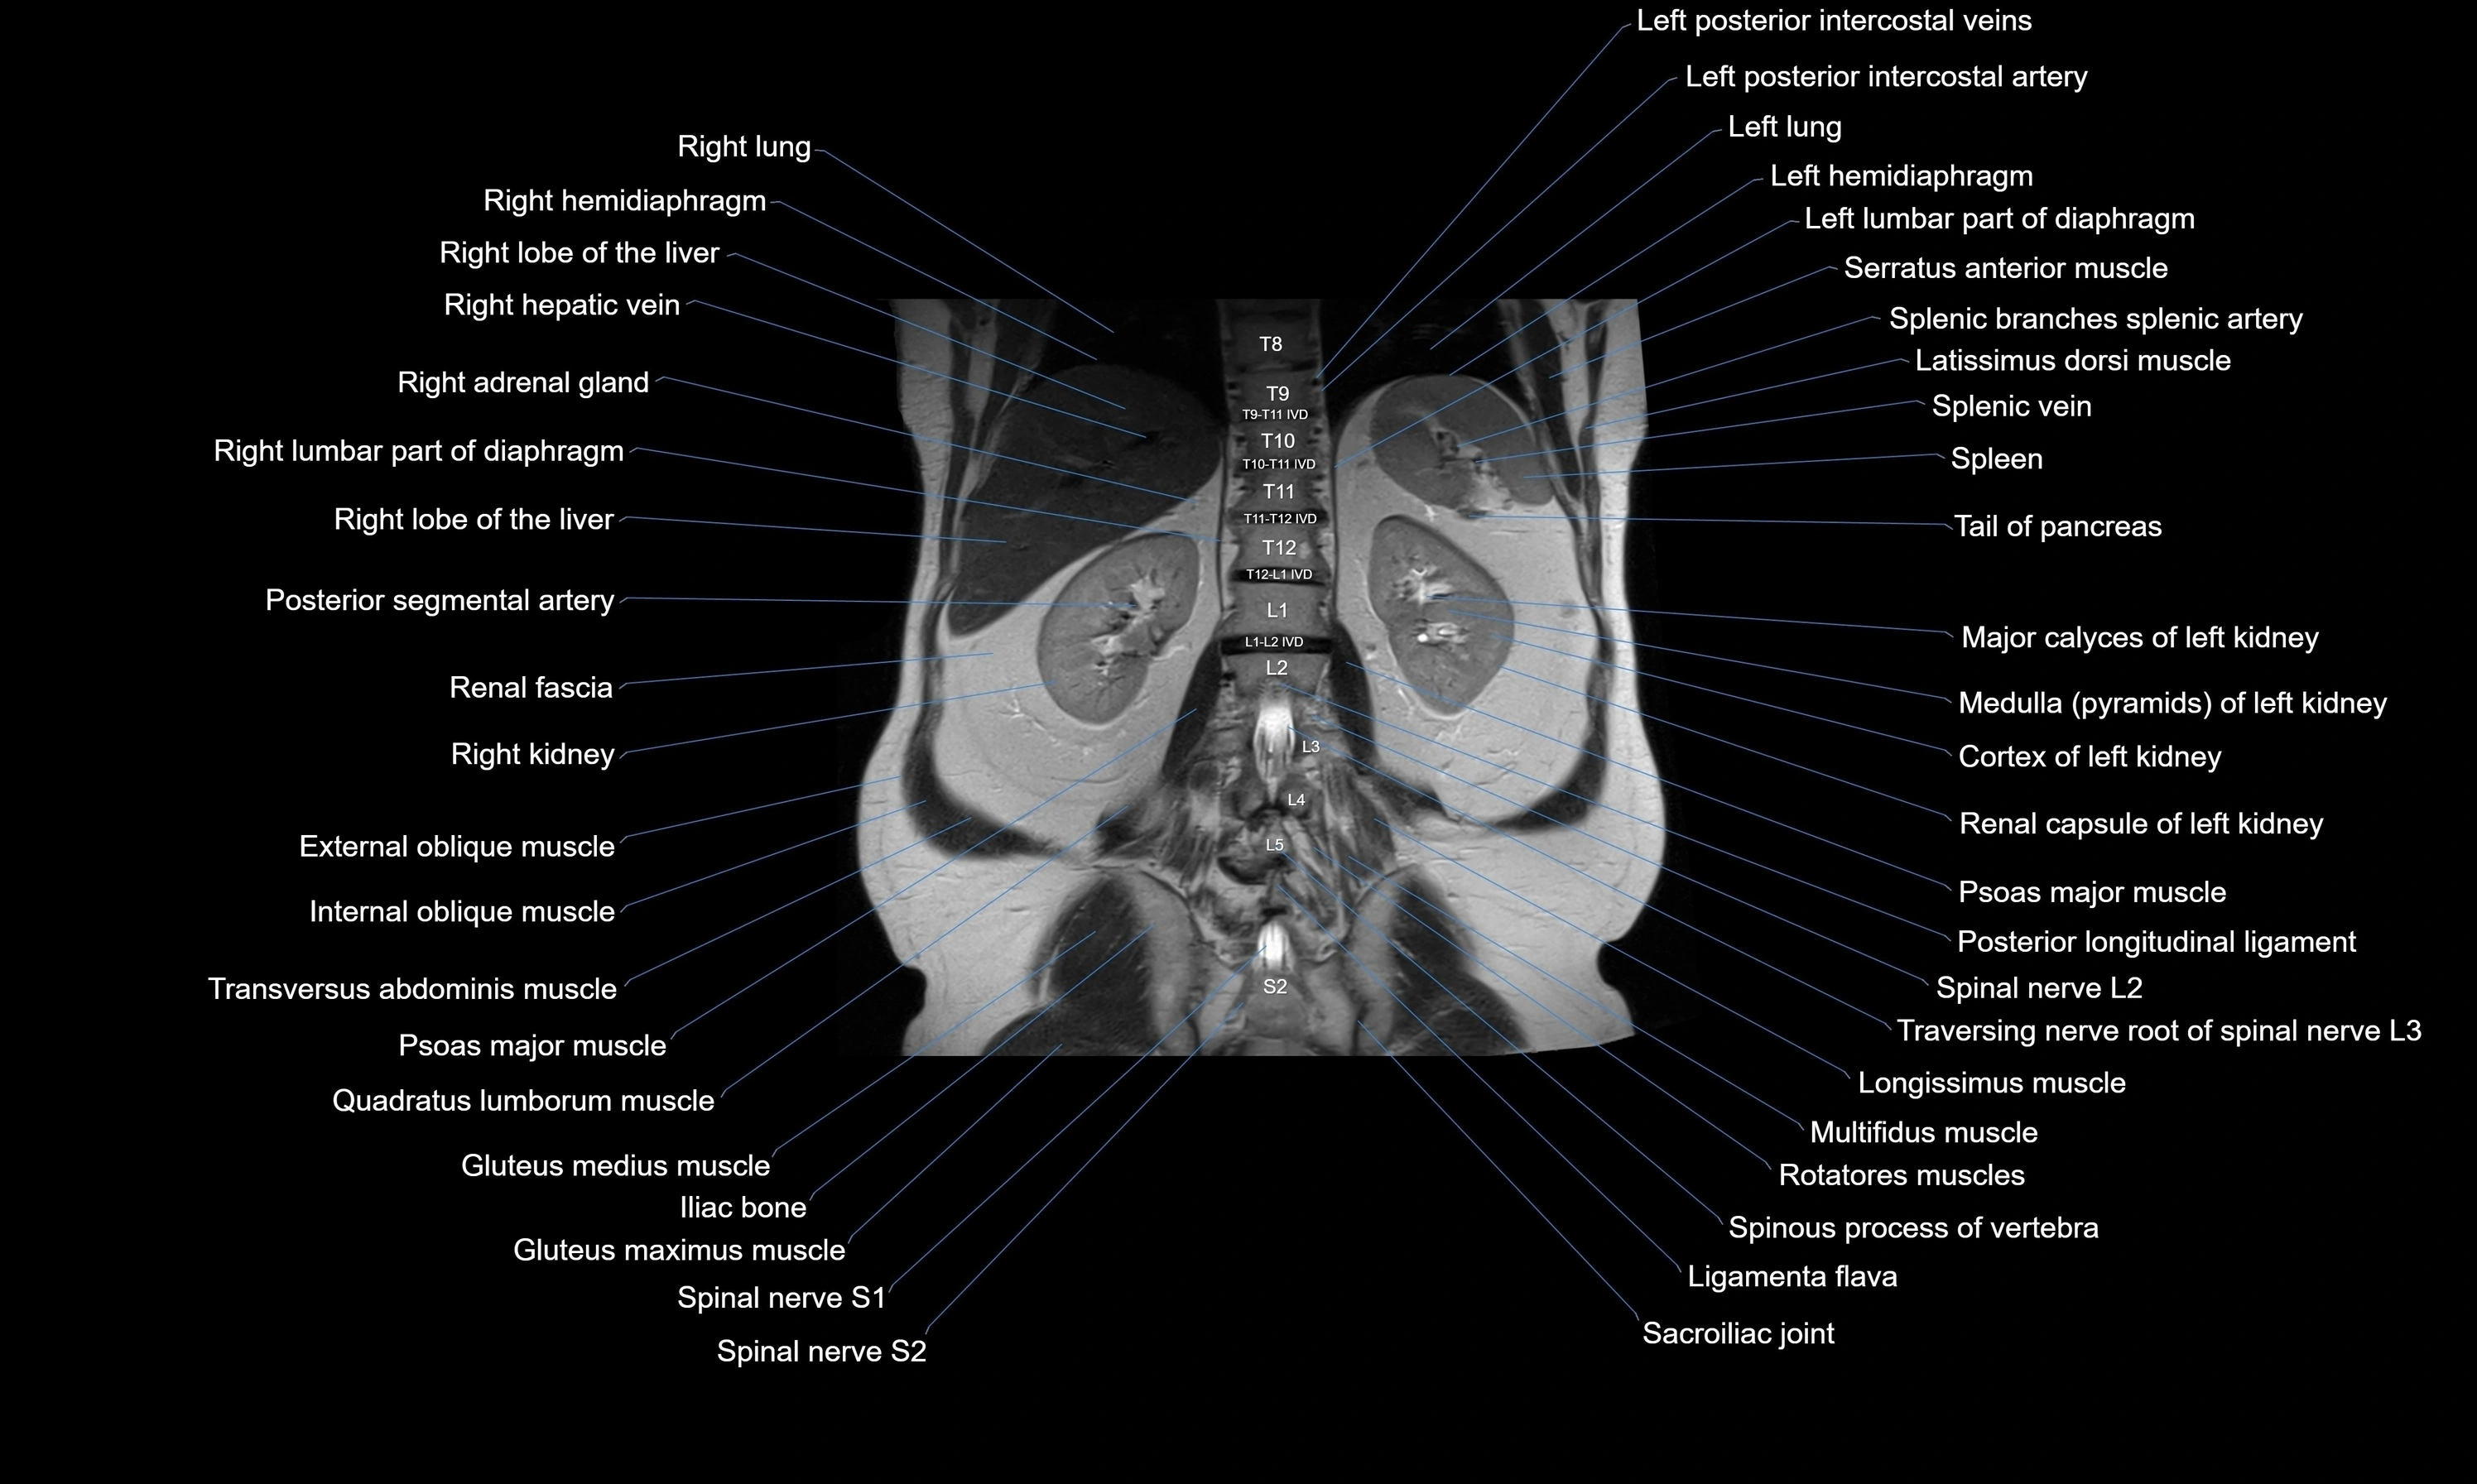

- Left kidney

- Ligamenta flava (Ligamentum flavum)

- Posterior longitudinal ligament

- Psoas major muscle

- Quadratus lumborum muscle

- Right kidney

- Spinal nerve L1

- Spinal nerve L2

- Spinal nerve L3

- Spinal nerve L4

- Spinal nerve L5

- Spinal nerve S1

- Spinal nerve S2

- Spleen

- Tail of pancreas